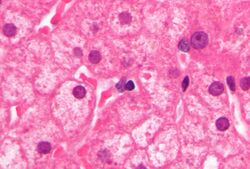

PCR tests have been developed to detect and measure the amount of HBV DNA, called the viral load, in clinical specimens. These tests are used to assess a person's infection status and to monitor treatment.[68] Individuals with high viral loads, characteristically have ground glass hepatocytes on biopsy.